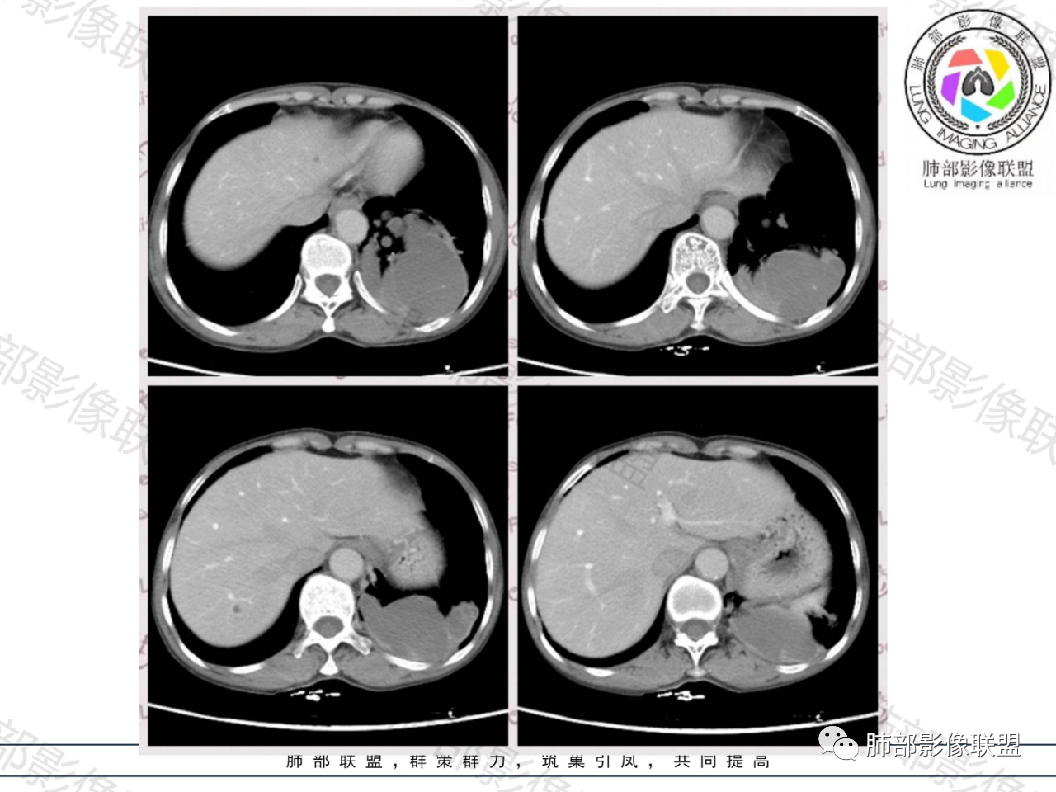

结果还是:肺隔离症

这个病理结果结合影像,有明显的体循环动脉供血血管进入病灶,诊断隔离肺 没问题

定义:肺隔离症也称为有异常动脉供血的肺囊肿症,是临床上相对多见的先天性肺发育畸形,为胚胎时期一部分肺组织与正常肺主体分离,单独发育并接受体循环动脉的异常动脉供血,所形成无呼吸功能囊性包块。

供血:体动脉供血,多来自胸主动脉下部或腹主动脉上部,较为粗大,直径0.5~2cm,异常动脉多在下肺韧带内,经下肺韧带到达病变部位

二、肺隔离症病理谱系

•支气管的狭窄---肺气肿

•支气管部分(有几支闭塞)堵塞---中央实变加周围肺气肿

•支气管几乎完全堵塞---完全实变,没有肺气肿,但容易感染

•支气管完全闭塞---完全实变,不容易感染